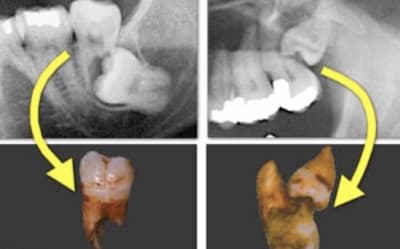

Bah alors ! Ben bien entendu qu’il faut les laisser en place ! Ça ne cause aucun problème...

8DE0A1E8-2DD0-4D53-A097-9BB4EBF20214_c1hzlx.jpg

AC10A55A-5FE5-4EEF-8BC3-48CE8E842DE0_wmi4kc.jpg

AB108EDA-34AF-4F84-AF10-998952ADDB29_ul6tfn.jpg

8243588C-A2F4-4BDC-B073-E1B3D70BBDF4_ok8qx5.jpg

E561E138-B7BA-4F34-AC1D-E238600B02A9_w4mrpg.jpg

27A0EF84-30D2-474C-B7F5-DD3F605A0909_zd09jn.jpg

ED7428F9-3851-4AF0-BDDB-192CED35661C_rcvw5y.jpg